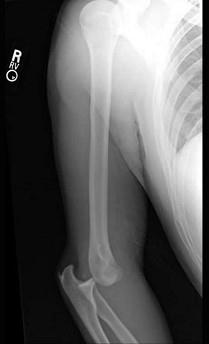

图示脱位最常见的为 ( )A、内侧方脱位B、骨折+脱位C、前脱位D、后脱位E、外侧方脱位

问题 图示脱位最常见的为 ( )

选项 A、内侧方脱位 B、骨折+脱位 C、前脱位 D、后脱位 E、外侧方脱位

答案 D